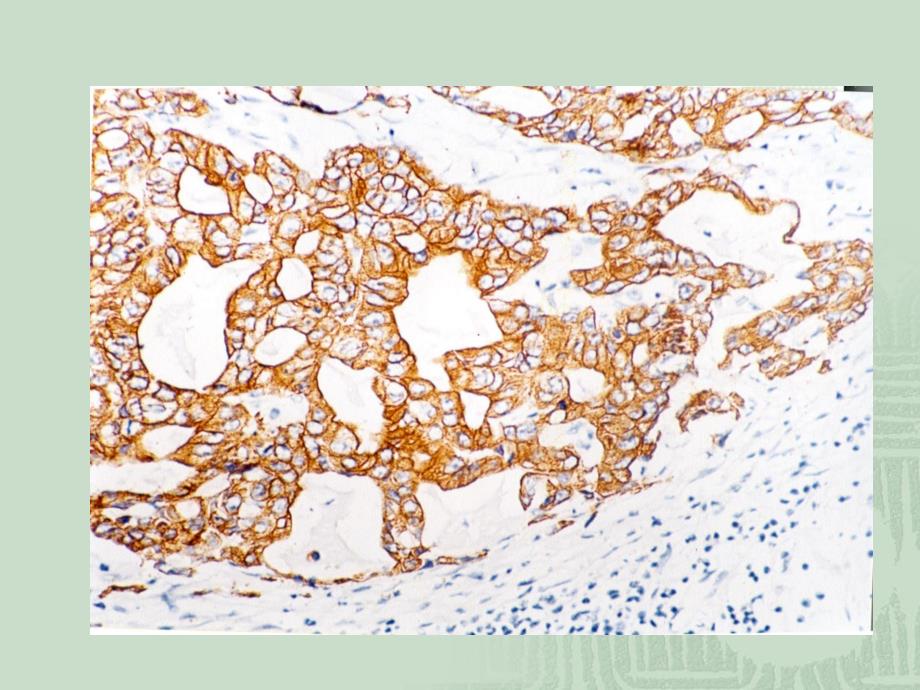

1、免疫组化结果判断免疫组化结果判断及常见问题分析及常见问题分析肝脏:肝脏:CK8理想着色,胆管上皮细胞强阳性,理想着色,胆管上皮细胞强阳性,肝细胞呈不同层次阳性。肝细胞呈不同层次阳性。pan CK(AE1/AE3)在肝脏理想的染色,采用了热修复。在肝脏理想的染色,采用了热修复。肝细胞膜、胆管强而清晰的着色。背景干净。肝细胞膜、胆管强而清晰的着色。背景干净。一、特异性染色的判断一、特异性染色的判断1.特定的定位特定的定位 细胞阳性细胞阳性根据靶抗原不同而呈现胞膜型、胞浆型根据靶抗原不同而呈现胞膜型、胞浆型 或胞核型或胞核型 间质阳性间质阳性表现为细胞外着色,局限性或弥散性表现为细胞外着色,局限性或

2、弥散性2.染色的不均一性染色的不均一性 阳性细胞的染色分布不均,片状或点状散在分布阳性细胞的染色分布不均,片状或点状散在分布 染色强弱不等,颜色深浅反映抗原量的多少染色强弱不等,颜色深浅反映抗原量的多少 3.排除人为造成的非特异性染色排除人为造成的非特异性染色 切片的折叠、刀痕,色素沉着,组织细胞坏死。切片的折叠、刀痕,色素沉着,组织细胞坏死。4.颗粒性显色颗粒性显色 DAB显色在高倍镜下呈颗粒状而非均匀着色。显色在高倍镜下呈颗粒状而非均匀着色。免疫组化标准化照片免疫组化标准化照片CK10CD44v6ER合格合格的免疫组化染色切片的免疫组化染色切片是正确判断染色结果的基础和前提是正确判断染色结

3、果的基础和前提不合格不合格的免疫组化染色切片的免疫组化染色切片容易导致误判容易导致误判C-erbB-2优优良良中中差差4321ER子宫内膜子宫内膜PR染色,修复不足染色,修复不足 子宫内膜子宫内膜PR染色,修复良好染色,修复良好 PR编号编号阳性片阳性片待检片待检片阴性对照阴性对照结论结论12345 操作失误,抗体失效操作失误,抗体失效非特异性着色非特异性着色阳性片不含靶抗原阳性片不含靶抗原待检片不含定位抗原待检片不含定位抗原待检片含定位抗原待检片含定位抗原二、染色结果的判断二、染色结果的判断PCNA S-P400S-P4001-day CM4-day CM阳性强度阳性强度2010视野下,随机